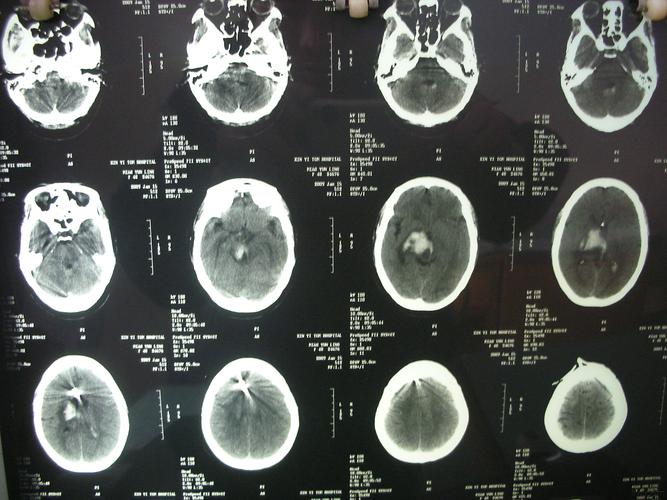

查体:bp:120|70mmhg,昏迷,压眶反射存在,双侧瞳孔不圆,直径约5.